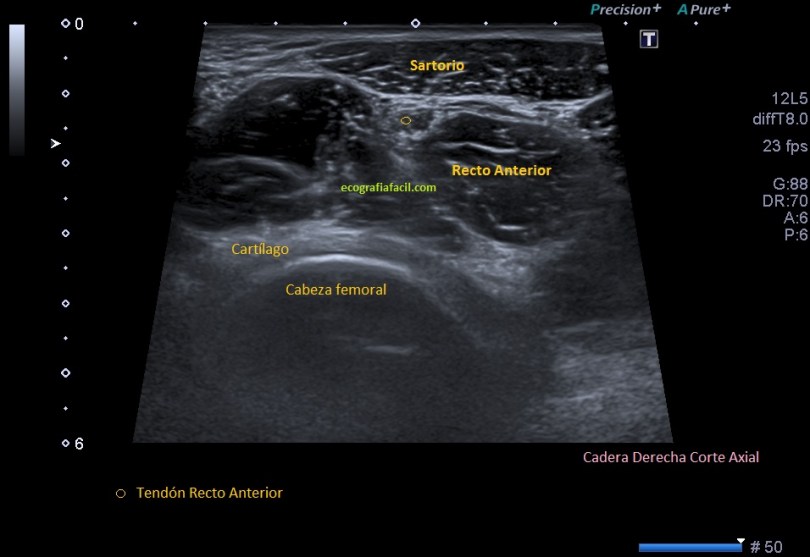

Repasamos anatomía y aprender una forma de estudio de la inserción del tendón del recto anterior del cuadricipital donde vas a ver esas fibras, perfectas. Como se tiene que ver para buscar entensopatías a ese nivel y para que las reconozcas en otras localizaciones típicas, aquiles, epicóndilo…etc…

Lo primero que hice fue tumbar al paciente en la camilla, con una sonda de alta frecuencia posicionada en la zona de dolor, explorando dicha zona en eje largo respecto del fémur, es decir, corte longitudinal.

Evidentemente es una imagen patológica comparada con una normal contralateral, la anatomía de la región patológica está cambiada, el hueso está irregular, comparativamente con la zona normal. Esos cambios en el hueso se visualizan en la espina iliaca inferior, donde inserta el tendón del recto anterior, pero este tendón no solo inserta fibras ahí, sino que algunas de ellas insertan justo en la región superior del acetábulo,imagen 3, es decir, justo antes de la inserción en la espina iliaca anteroinferior, algunas se bifurcan hacia profundo, buscando el acetábulo.

Explorar esta zona de inserción es complejo, el recto anterior, que luego es el tendón intramuscular o rafe del recto anterior del cuadriceps, inserta mediante su tendón buscando la profundidad en la cadera, con lo que encontramos anisotropía…te voy a enseñar una forma de explorarlo donde vas a poder corregir esa anisotropía. La exploración habitual es con la pierna en extensión y decúbito supino, pero vamos a pedir al paciente que se siente en la camilla, baje la pierna y apoye el talón del pie, el tronco del paciente mínimamente inclinado hacia atrás, la cadera y la rodilla en extensión y la sonda colocada en la zona de inserción…la imagen que logras es esta maravilla, imagen 3.

En la imagen número 5 puedes ver el corte axial de la imagen 4, como a tres centímetros de la inserción. Puede estar ligeramente modificada la angulación para corregir anisotropía del tendón, y me parece una imagen muy bonita, el recto anterior es externo.

En el corte axial puedes observar el tendón del recto anterior, que ya no intramuscular, ya no el rafe, como ves en la imagen 6:

El corte ya no es en el muslo, es prácticamente en la cadera, y lo importante es seguir bien en las dos proyecciones el tendón.